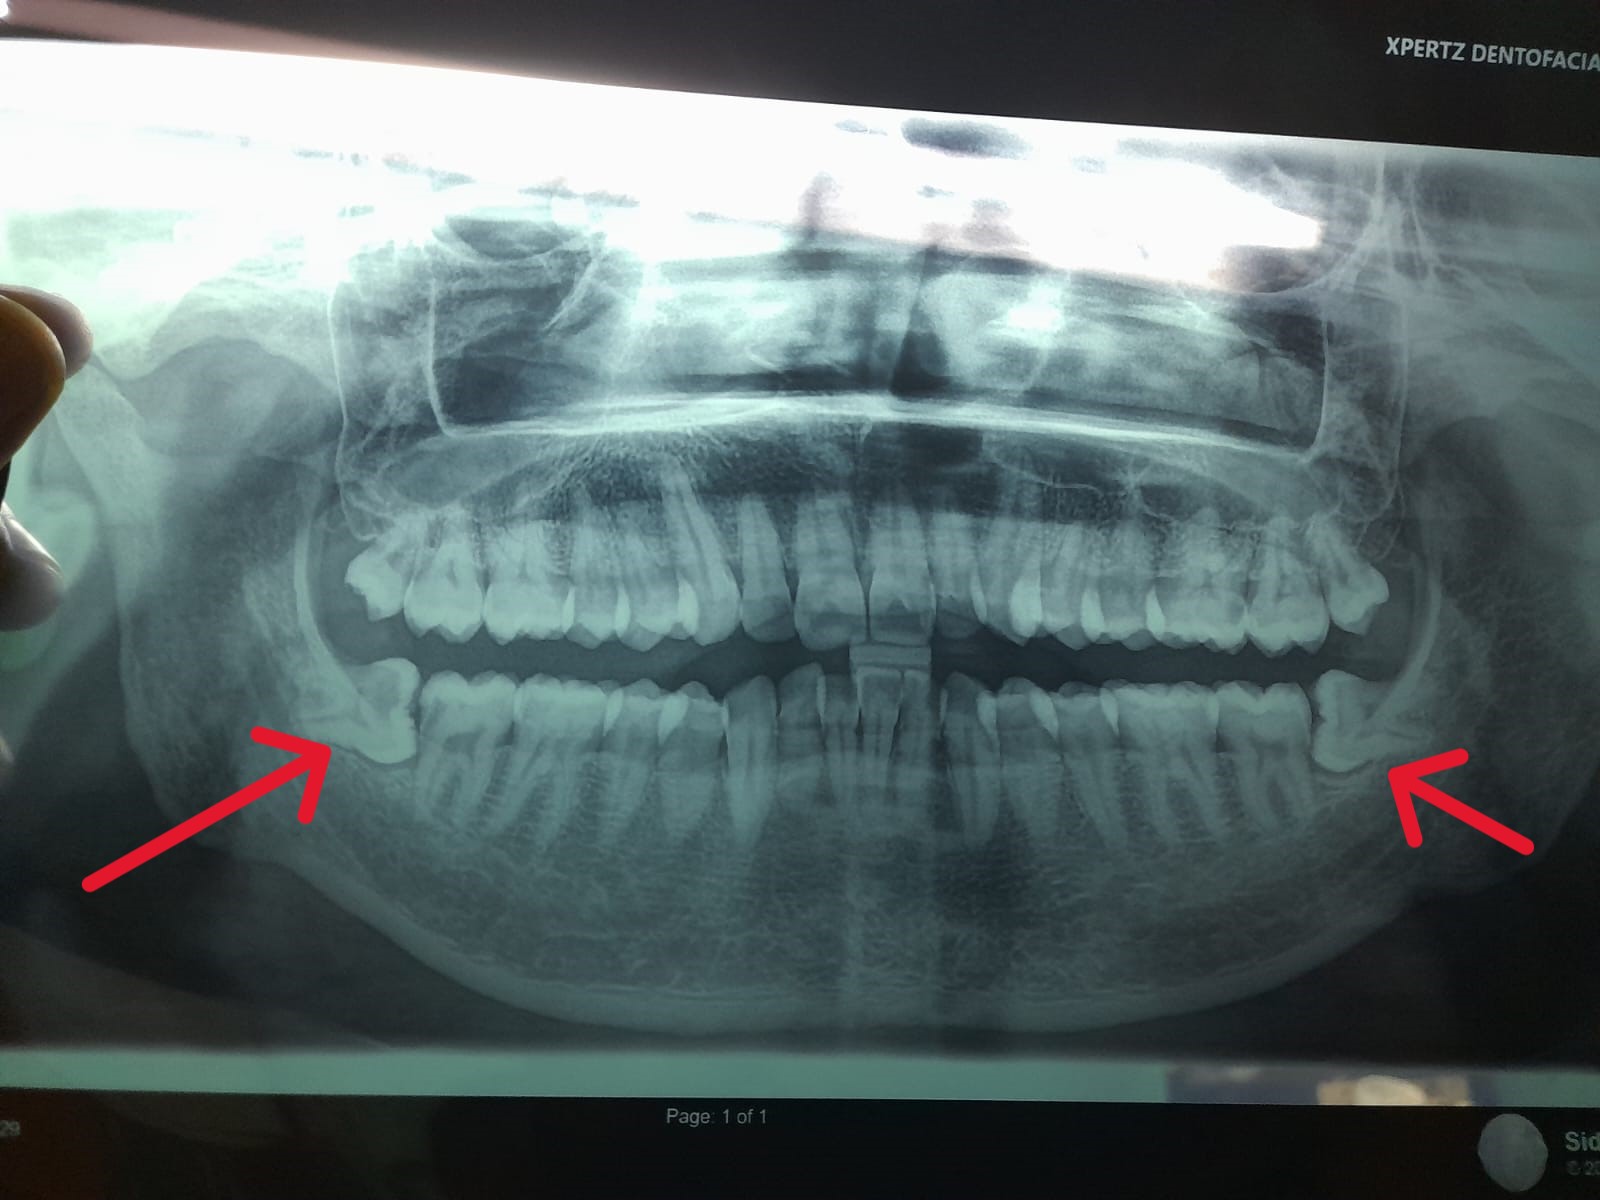

Below image is a wisdom teeth grow in an atypical direction, coming out sideways, at an atypical angle, or only partially. This wisdom teeth that grow in different direction (position). It causes pain and damage it adjacent teeth. It is also damage occurs. In most of people do not remove their wisdom teeth. If pain occur consult dentist.